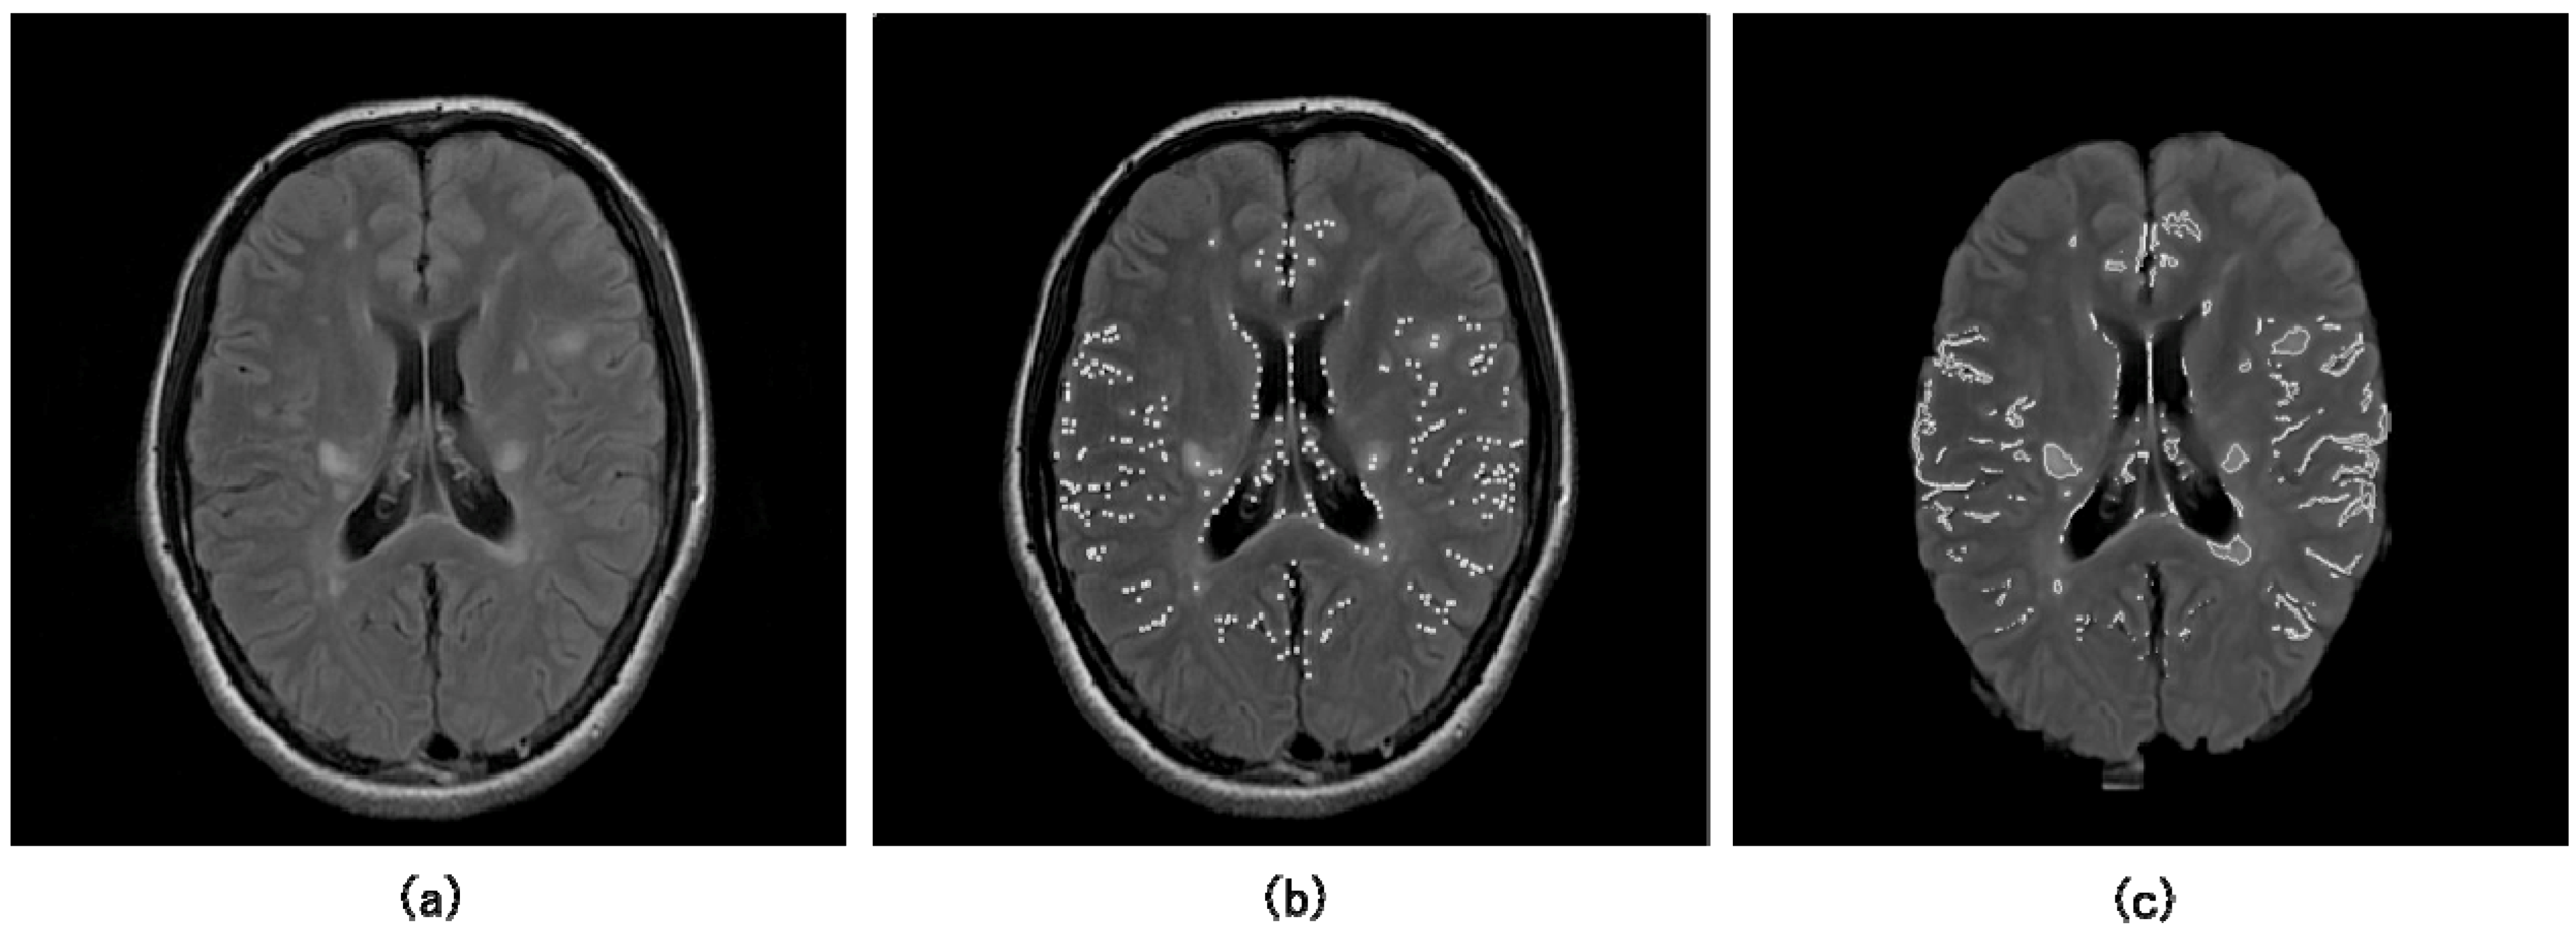

Although a number of methods for initial detection of lesions have been developed in the CAD field, basic simple thresholding techniques for outputs of enhancement filters or pixel values in the object-enhanced images have been employed for initial identification of lesions. As a unique method, Lee et al. developed an initial detection method of lung nodules using two template matching techniques based on a genetic algorithm and cross-correlation coefficient [45]. Furthermore, although it may not be directly related to the initial lesion detection, a method based on probabilistic atlases has been developed for determination of some anatomical regions such as cerebral cortical regions [46,47]. Probabilistic atlases could store information on anatomic and functional variability in a population. We have applied a multiple-gray level thresholding technique developed by Giger et al. [21,43] to the neuroradiological CAD field, for detection of initial aneurysm candidates, white matter hyperintensities (WMHs) and MS candidates in MR images as the points with local maximum pixel values in candidate regions [25,26,28,30,31]. Figure 6 shows a FLAIR image including initial MS candidate points (white dots) obtained by the multiple gray level thresholding technique, and a brain image with initial candidate regions (white solid lines) segmented by the region growing technique [30,31].

Figure 6.

Illustrations of (a) an original FLAIR image, (b) initial MS candidate points (white dots) obtained by the multiple gray level thresholding technique, and (c) initial candidate regions (white solid lines) segmented by the region growing technique [30,31].